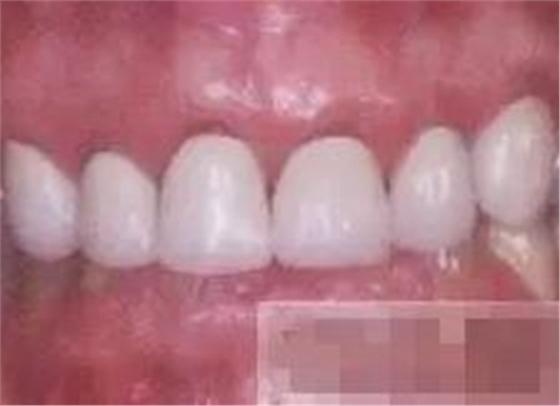

【充填完成】

1、樹脂貼面平齊牙齦邊緣是最佳設(shè)計(jì),或者使用齦上邊緣 。

2、釉質(zhì)邊緣要用橡皮輪拋光。拋光可以去除懸釉。這樣經(jīng)過車針打磨過的釉質(zhì)表面會(huì)更加均一,形成良好的邊緣封閉。

3、纖維樁通常深入到根管的1/2至2/3處。因?yàn)樽罴训恼辰有Чl(fā)生于根管的冠1/3和中1/3。由于根1/3的牙本質(zhì)小管往往不能充分敞開,此區(qū)域幾乎沒有粘接作用發(fā)生,所以,根管纖維樁放置的深度無需超過根中1/3。

4、修整纖維樁按所需長度裁截纖維樁 在有水條件下 用切割砂片或車針截取纖維樁,切勿使用鉗子,剪刀或鑷子以免破壞樁的結(jié)構(gòu)。

5、為了提高樹脂的聚合轉(zhuǎn)化率,我們可以用防氧化劑,或者用甘油涂沫于樹脂的表面,或者修復(fù)體的間隙處,以利于樹脂的聚合。然后再進(jìn)行打磨拋光。